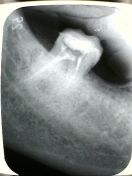

Nuova richiesta di visita, presenza di gonfiore accentuato, dolore vivo alla pressione nel fornice, eseguita Rx endorale che evidenzia il corretto trattamento endodontico, prescritta terapia antibiotica, la sintomatologia si risolve per alcune settimane.

La paziente si presenta all'appuntamento con completa remissione per trattamento antibiotico, oltre che antinfiammatorio per altri motivi, la fistola risulta non reperibile, si decide comunque di rispettare il piano di trattamento preventivato. Si inizia a rimuovere la ricostruzione che inaspettatamente viene asportata interamente come un tappo, a questo punto si evidenzia frattura mesio-distale che interessa tutto l'elemento, si procede quindi all'estrazione che avviene senza particolari problemi e che rivela la completa frattura in senso sagittale del dente in questione, si esegue toeletta chirurgica dell'alveolo, viene posizionato materiale sintetico osteoconduttivo, membrana e punti di sutura.